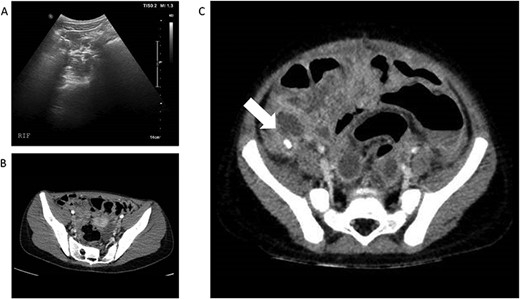

(A) and (B)—Case 1: abdominal ultrasound scan and computed tomography (CT) scan of abdomen, (C)—Case 2: CT scan of abdomen; white arrow shows faecolith with inflamed appendix and surrounding collections.

Examination findings revealed the patient to be mildly tachycardic but normotensive. She was apyrexial and had abdominal tenderness centrally and in the right iliac fossa and was reported to be Rosving’s positive. The patient had markedly raised C-reactive protein (CRP) and lymphopenia along with a high D-Dimer and elevated ferritin. Her transaminases were also noted to be mildly elevated (Table 1). Abdominal ultrasound scan (A-USS) demonstrated mesenteric adenitis without free fluid and chest X-ray was unremarkable. Within 12 hours of admission she developed a palmar rash, followed by shock. Urgent computed tomography (CT) scan of the chest and abdomen revealed diffuse intra- and interlobar thickening consistent with SARS-CoV-2 infection and no intra-abdominal pathology (Fig. 1A and B). She was SARS-CoV-2 negative on reverse transcriptase polymerase chain reaction. Patient A was treated successfully for PIMS-TS with supportive care including antibiotics until the blood cultures were negative and the interleukin-1 antagonist anakinra [3]. The patient underwent an echocardiogram on Day 8 and was found to have left coronary artery ectasia and has ongoing follow-up of this important sequelae of PIMS-TS.

Patient B, a 3-year-old boy, presented similarly with a 4 day history of abdominal pain, non-bilious vomiting and high temperatures. He had normal observations for his age but had abdominal distension and a tender lower abdomen. He also had a raised CRP along with an elevated D-Dimer and raised Ferritin (Table 1). A-USS and echocardiogram performed on Day 1 of admission were normal and he was SARS-CoV-2 positive on nasopharyngeal swab. Intravenous piperacillin and tazobactam were commenced to treat for possible concurrent sepsis and a presumptive diagnosis of PIMS-TS was made. Over the subsequent 12 hours he deteriorated with worsening pain and vomiting but it was noted that his CRP had reduced from 261 mg/L to 171 mg/L. Abdominal CT scan was undertaken and revealed perforated appendicitis with intra-abdominal collections (Fig. 1C). He underwent open appendicectomy without immediate complication and recovered well. He was treated for a superficial wound infection 7 days post-operatively with oral antibiotics.